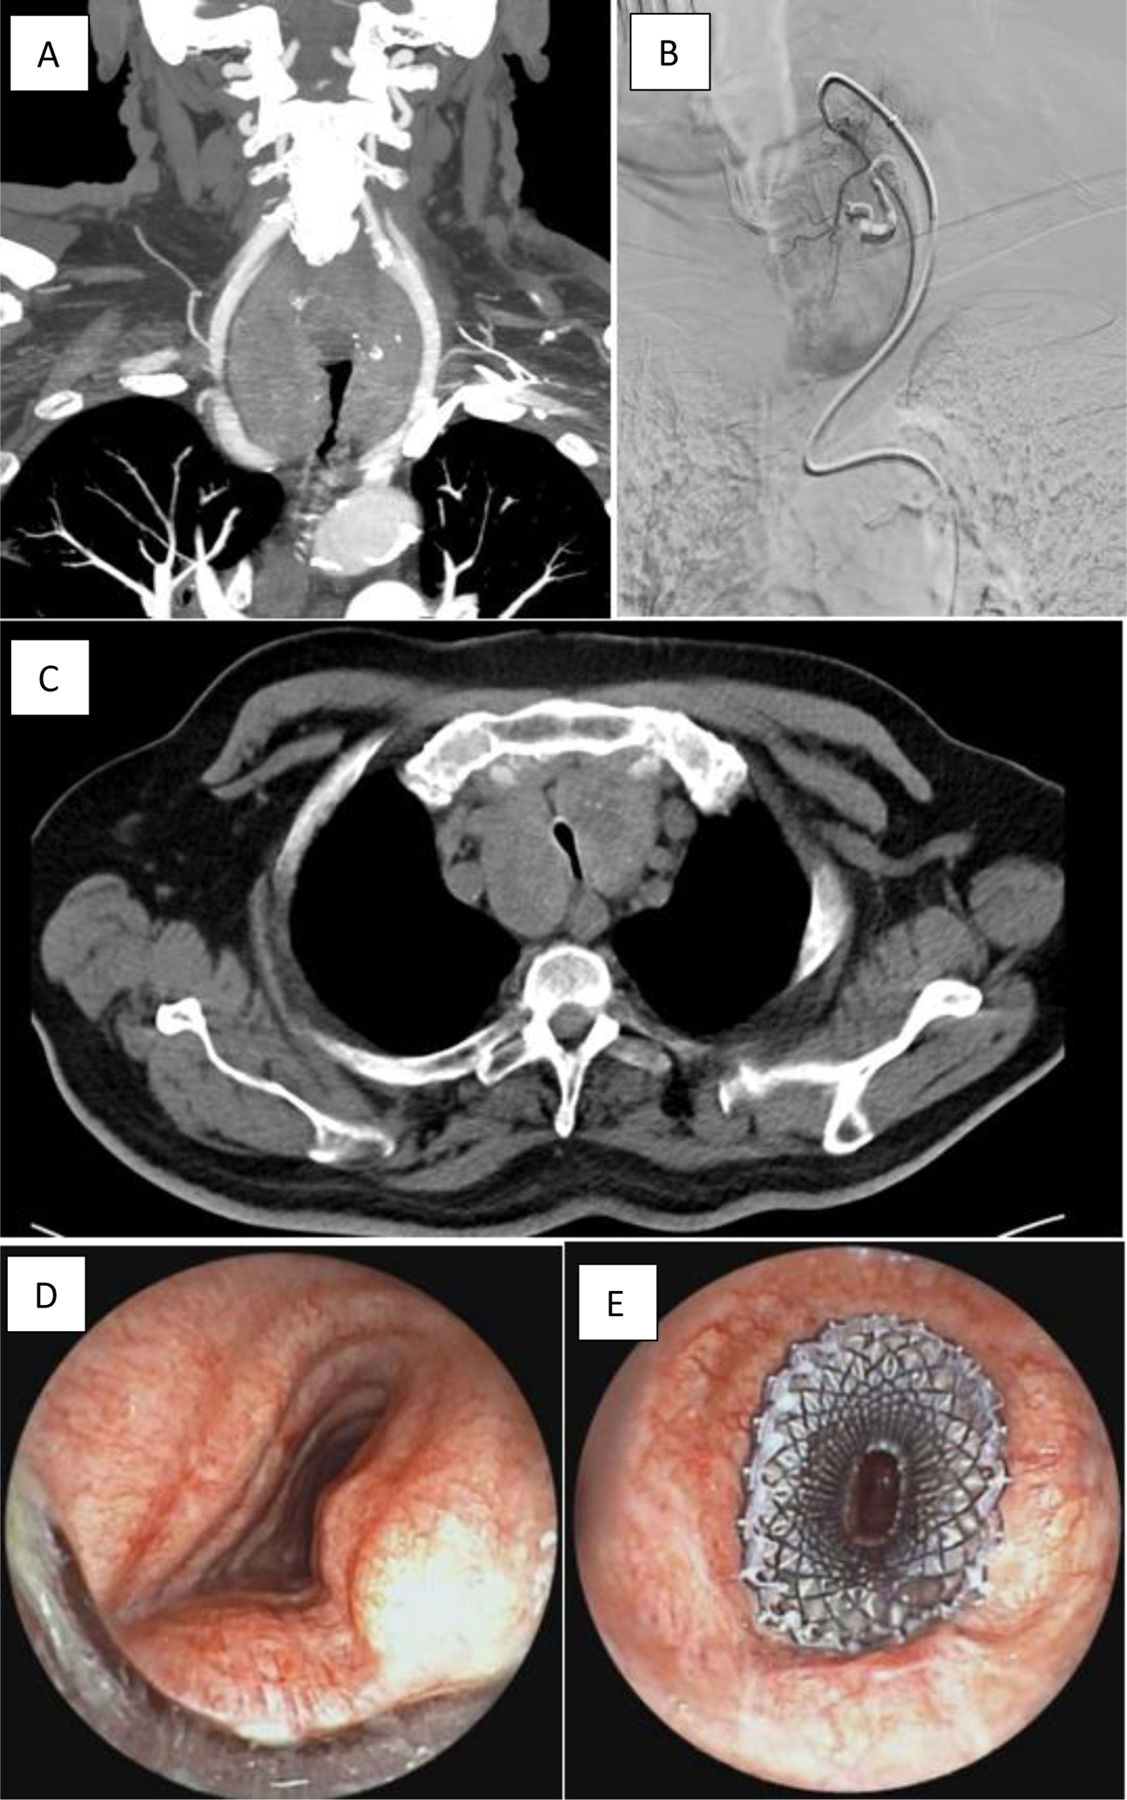

Endothoracic goiter may cause compression of the trachea [1]. Surgery is the first-line treatment [2], but in cases with extensive mediastinal involvement, sternotomy may be required, increasing morbidity and mortality. In elderly patients or those with significant comorbidities selective embolization of thyroid arteries (SETA) is a minimally invasive alternative [3]. We present the case of a patient with GOLD 4B COPD on long-term oxygen therapy and non-invasive ventilation (NIV), diagnosed with endothoracic goiter without suspicion of malignancy. The goiter caused a 80% proximal tracheal stenosis (Fig. 1), resulting in mMRC grade 4 dyspnea and a 6-minute walk distance of 72m on oxygen. Due to high surgical risk, SETA was performed. Post-procedure, the patient developed destructive thyroiditis with hyperthyroidism and refractory respiratory acidosis, preventing NIV weaning. Under general anesthesia, rigid bronchoscopy revealed a 3cm long, laterolateral proximal tracheal stenosis with a residual lumen of ∼6mm. A self-expanding metallic stent [4,5] (LEUFENT Aerstent TBS 20×40) was placed, with the proximal end 3cm below the glottis. Endoscopic outcome was satisfactory, allowing NIV weaning and subsequent discharge. Stent removal is planned following resolution of thyroiditis. This approach can effectively relieve tracheal obstruction and improve clinical outcomes, highlighting the importance of individualized, multidisciplinary management strategies.